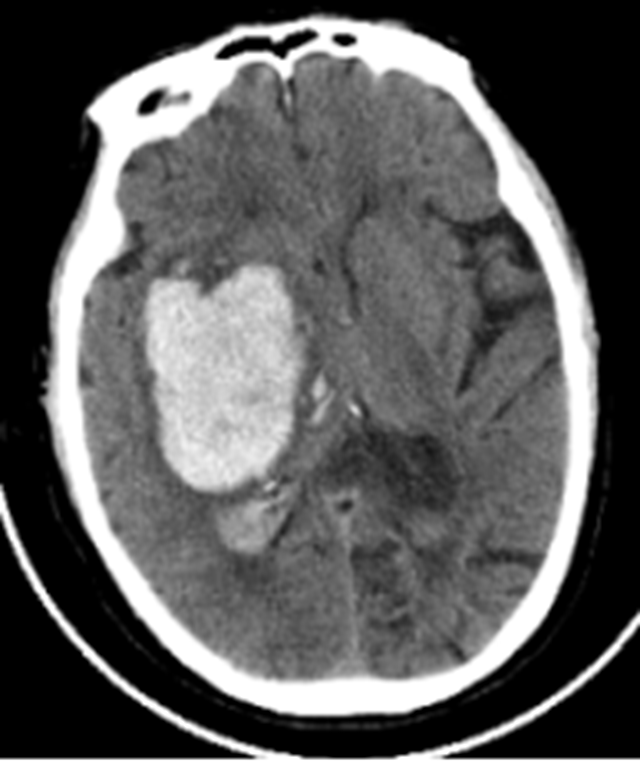

说起卵巢癌大家可能有点陌生但它却被称“妇科第一癌”因为在所有的妇科肿瘤中甚至全身各器官系统的恶性肿瘤中卵巢癌都是最棘手的癌症之一而且发病隐匿超过70%的患者确诊时已是晚期是死亡率最高的妇科癌症王永周教授主任医师妇科主任兼妇产科副主任擅长宫颈...